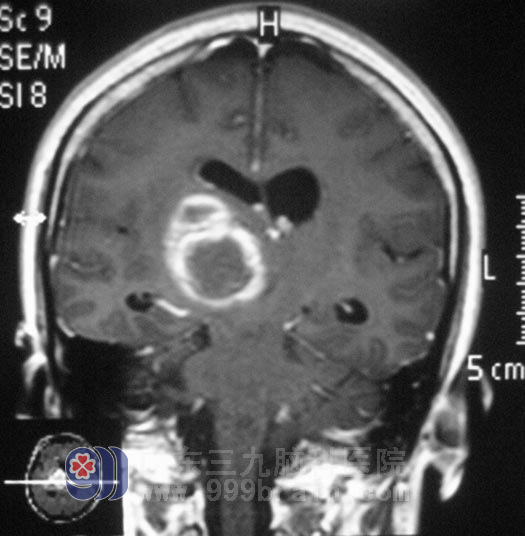

在广东三九脑科医院综合神经外科,通过MR、DSA检查,鲁明主任考虑病变部位为海绵状血管瘤。完善相关检查后,由鲁明主任主刀,在唤醒麻醉下行右侧基底节区、丘脑海绵状血管瘤切除术+血肿清除术,显微镜下切除右侧基底节区、丘脑处海绵状血管瘤及陈旧血肿,对她的语言及肢体运动功能完好保护。治疗后,姚女士术前症状基本消失,行走自如。术后病理结果为:海绵状血管瘤。

▲手术前